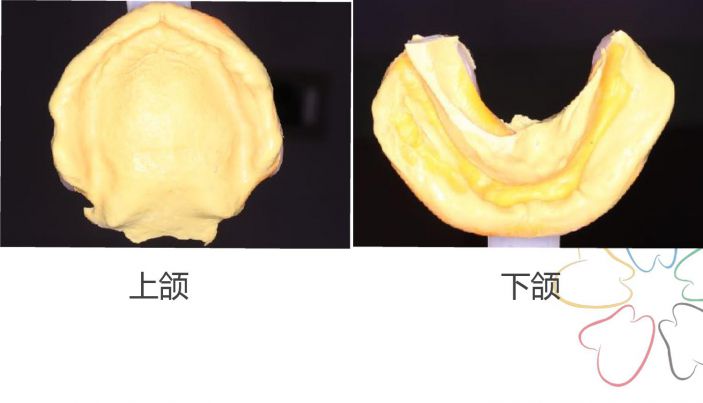

二、初印模